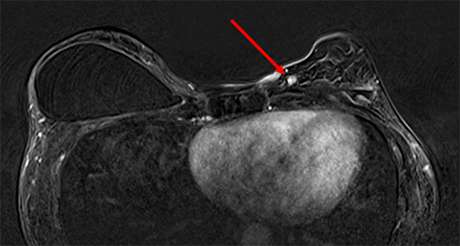

Approximately two-thirds to three-quarters of cancers present as a mass (4). Mass is defined by BI-RADS as a 3-dimensional lesion occupying space within the breast. Similar to mammography and sonography, masses are described by their shape, margins, internal characteristics as well as MRI contrast enhancement pattern (Figure 2).

Breast masses are categorized into 3 shapes: oval (including lobulated), round, and irregular. Margins are described as either circumscribed or not circumscribed (including irregular and spiculated margins) (5). Enhancement patterns are described as homogenous, heterogenous, rim enhancement, and dark internal septations. Mass features suspicious for malignancy include irregular size and margin, heterogenous or rim enhancement and washout kinetics (5).